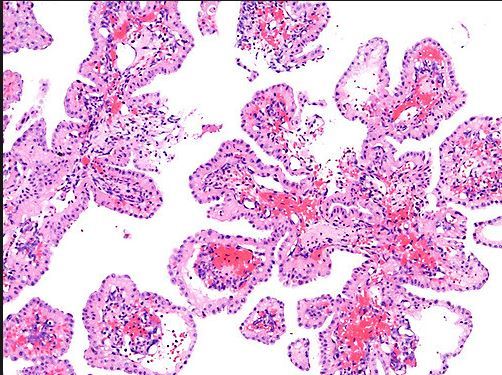

Which ear tumor arise in the temporal bone, is benign, locally destructive, rare, M=F, 2nd – 8th decade, has association with VHL disease, is papillary and cystic with colloid-like material (PAS+), has bland cuboidal to columnar cells, eosinophilic to clear cytoplasm and is postive with keratin but negative for thryoglobulin?

Interestingly, the nuclei are situated AWAY from the base

A

Papillary Endolymphatic Cell Tumor which is also known as a Heffner tumor

D/D: PTC, RCC, adenoca, mid. ear adenoma